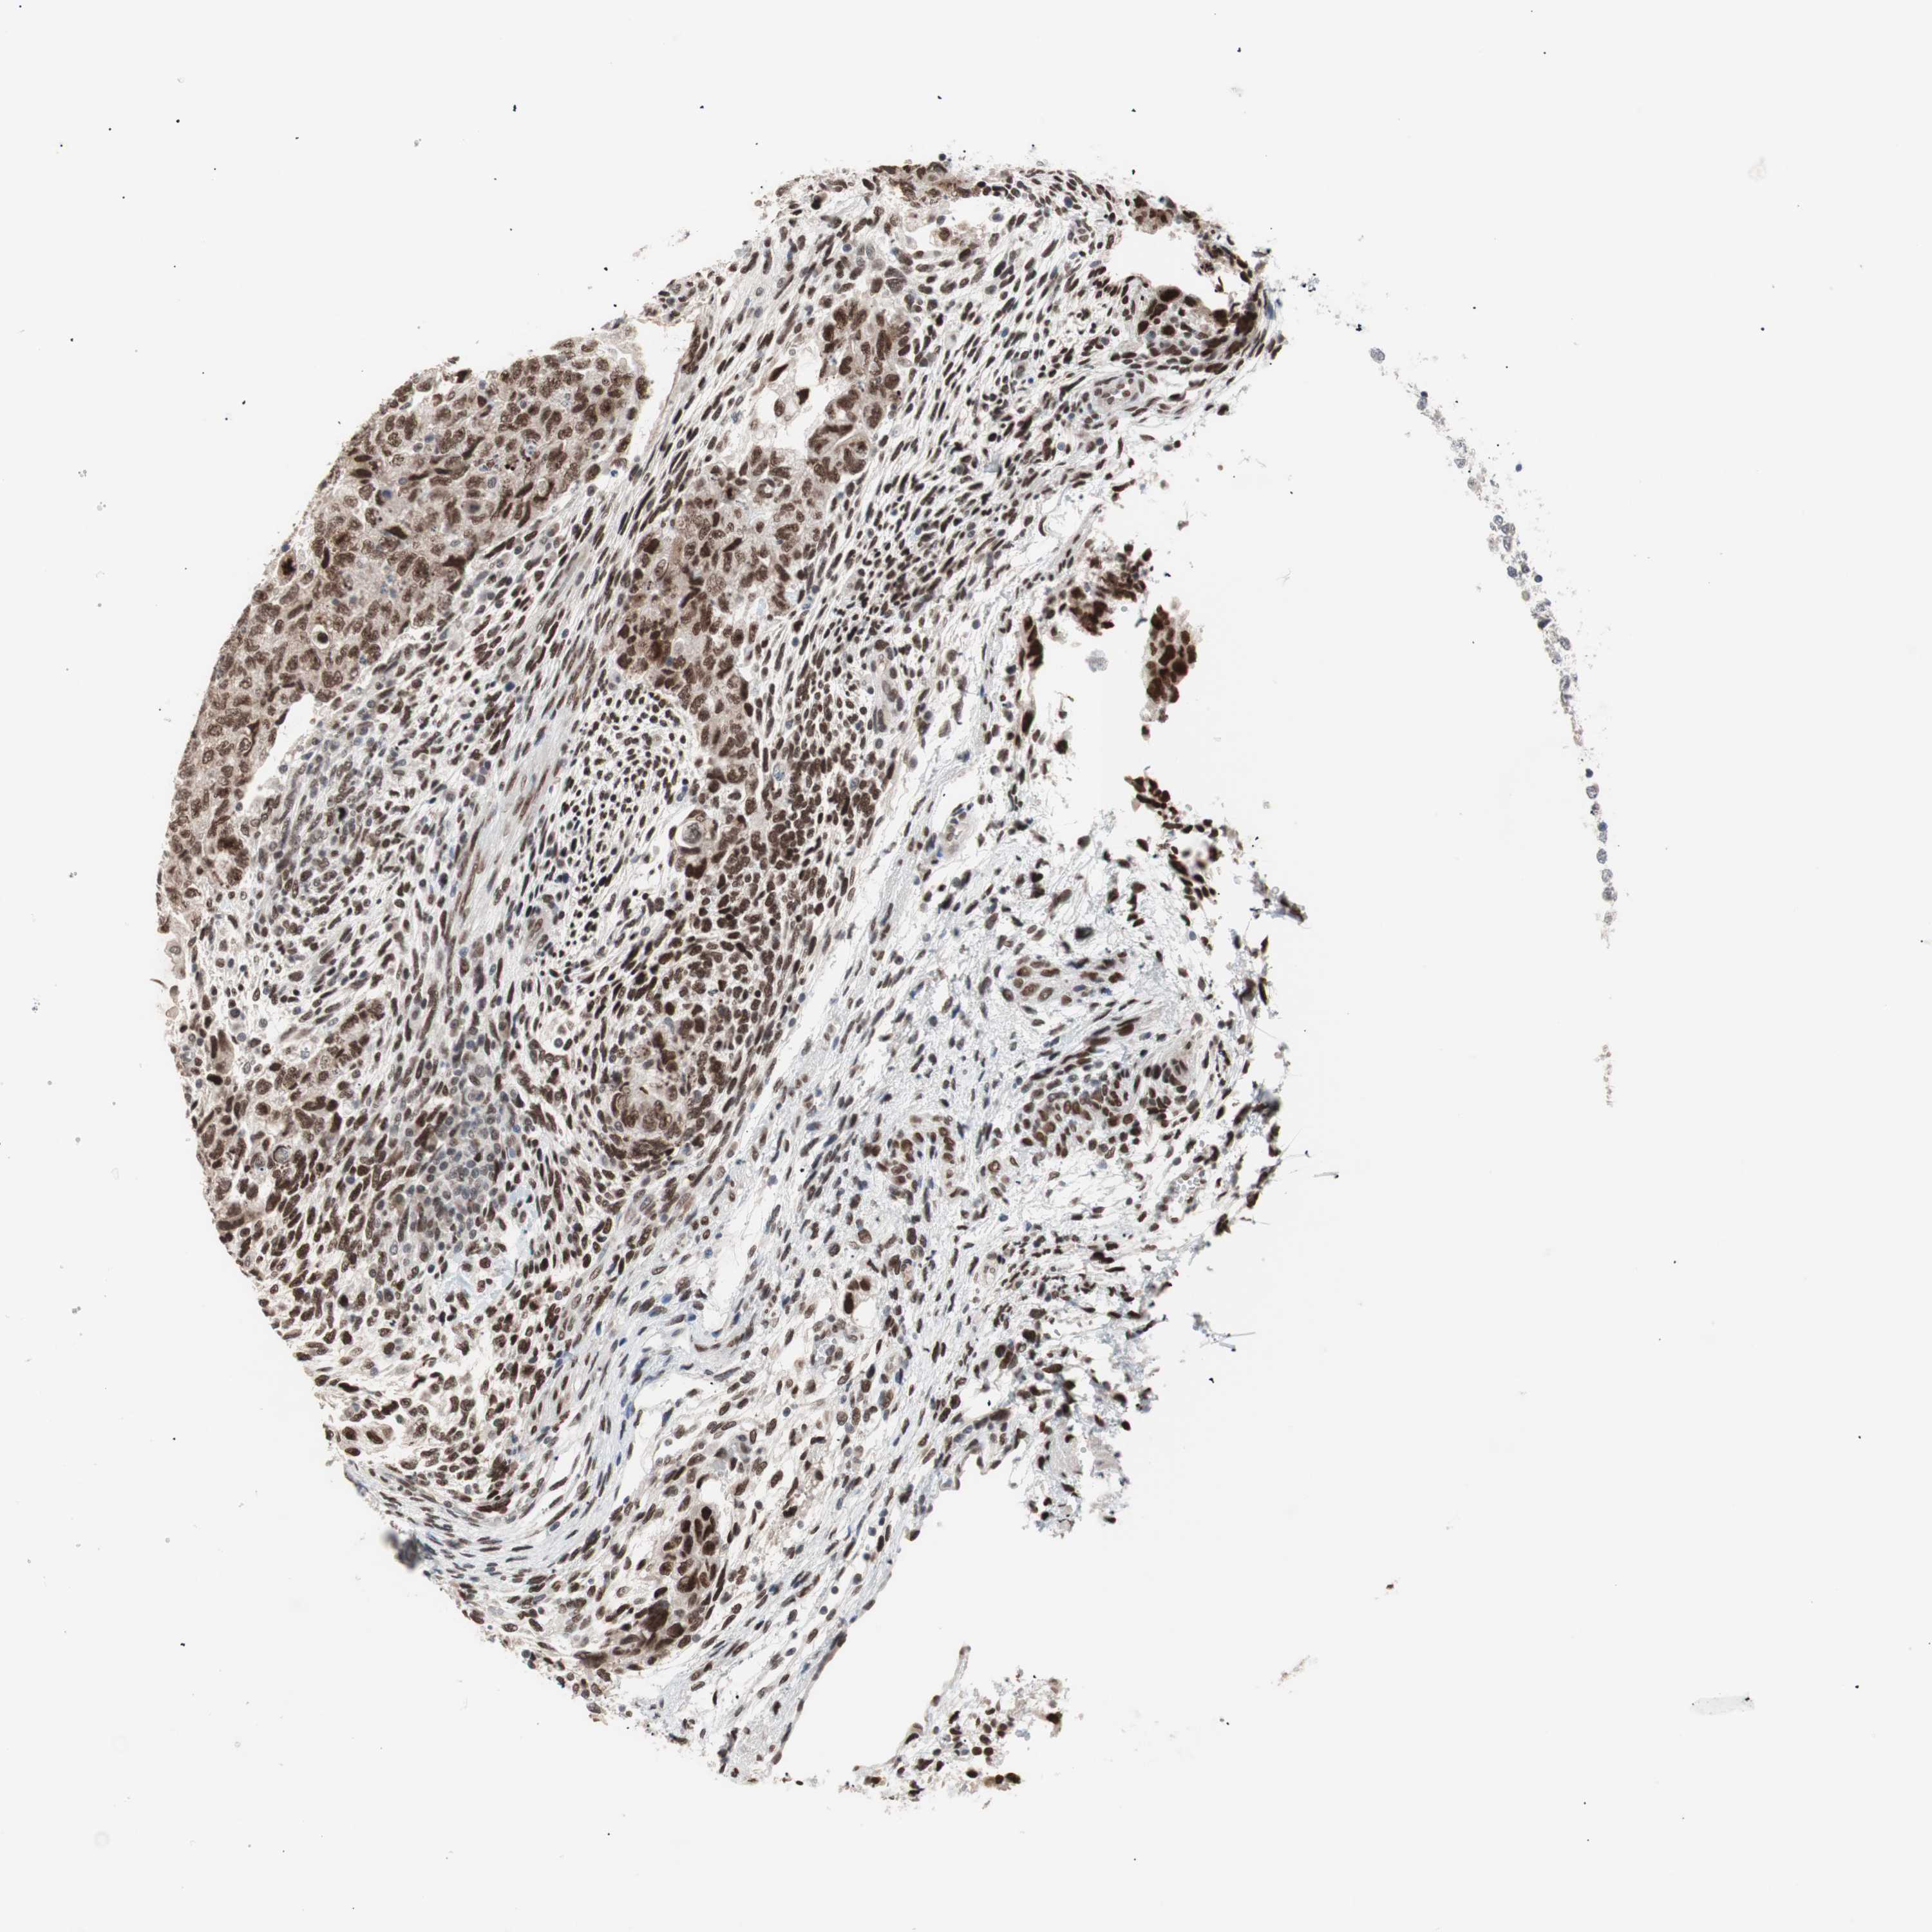

Antibody HPA006723

Antibody CAB080348

Staining

High

Medium

Low

Not detected

Intensity

Strong

Moderate

Weak

Negative

Quantity

>75%

75%-25%

<25%

None

Location

Carcinoma, Embryonal, NOS

Seminoma, NOS

TESTIS CANCER - Protein expressioni

A mouse-over function shows sample information and annotation data. Click on an image to view it in a full screen mode. Samples can be filtered based on level of antibody staining by selecting one or several of the following categories: high, medium, low and not detected. The assay and annotation is described here.

Note that samples used for immunohistochemistry by the Human Protein Atlas do not correspond to samples in the TCGA dataset.

Antibody stainingi

Antibody staining in the annotated cell types in the current human tissue is reported as not detected, low, medium, or high, based on conventional immunohistochemistry profiling in selected tissues. This score is based on the combination of the staining intensity and fraction of stained cells.

Each image is clickable and will lead to virtual microscopy that enables deeper exploration of all samples and also displays staining intensity scores, fraction scores and subcellular localization as well as patient and tissue information for each sample.